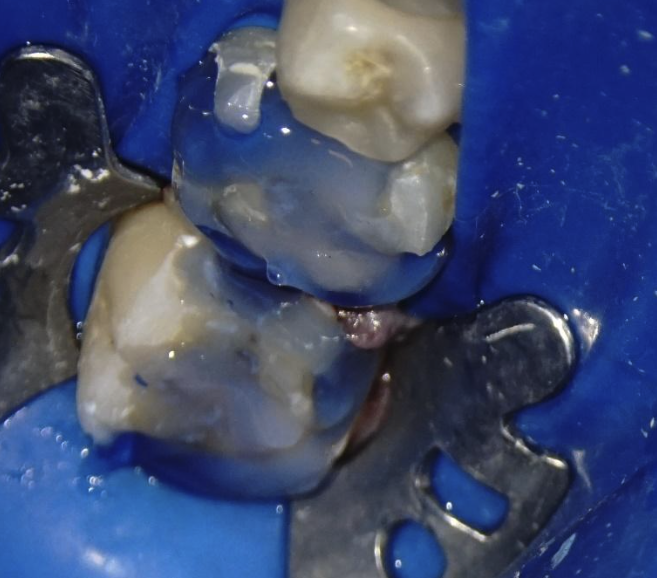

Utilizarea microscopului mi-a permis îndepărtarea mai precisă a zonelor de smalț cretos cariat (Fig. 3. Săgeata roșie indică zona de smalț cretos) prezent la marginea dintelui ce pot fi mai greu de indentificat, și ca urmare pot duce la apariția ulterioară a cariei lângă restaurarea finală. Această coleretă de smalț de la marginea dentară, care trebuie să fie bine lustruită și lipsită de carie, reprezintă punctul cheie în asigurarea unei restaurări durabile, la acest nivel asigurându-se cea mai mare putere de adeziune a materialelor de cimentare.

Figura 3. Prezența smalțului cretos ce poate duce la apariția ulterioară a cariei marginale